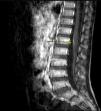

Ante la sospecha clínica de mielitis motivada por la presencia de hiperreflexia y tetraparesia, se inició pauta corta de corticoterapia oral con leve mejoría sintomática. Se indicó resonancia magnética (RM) craneal y medular. Mientras que en la RM de cráneo no se detectó ninguna alteración, en la columna lumbosacra se objetivó una captación de gadolinio en las raíces de la cauda equina (fig. 1), compatible con radiculitis inespecífica.

Si bien los hallazgos en la RM suelen ser inespecíficos, estudios sobre el SGB en edad pediátrica5 describen realces del contraste a nivel de las raíces espinales en la mayoría de los casos.